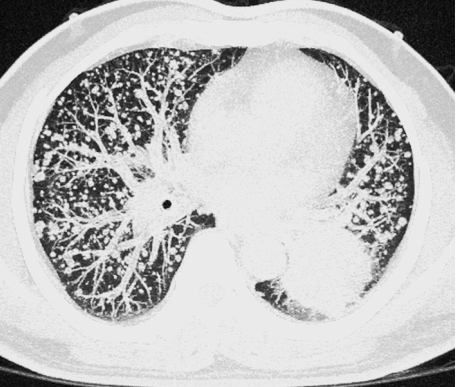

我们知道,辐射是很多人担心的问题之一。飞利浦Incisive AI CT拥有不限体型、不限部位的临床化低剂量成像,大幅抑制噪声的同时提高图像对比度,保障图像质量满足临床诊断要求。

▲ 肺内结节、无处隐藏